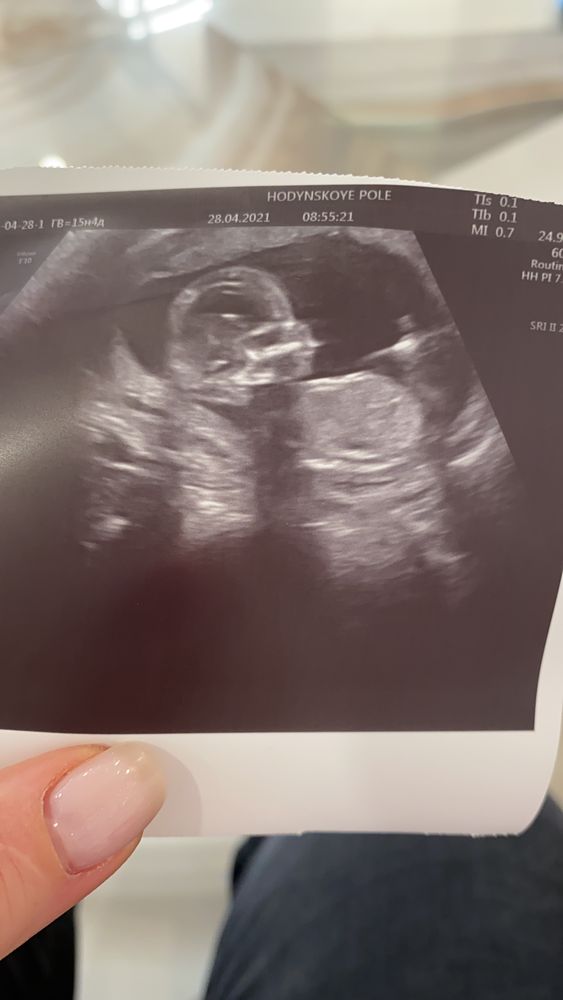

Наши 16 недель

Сходила сегодня на узи, по показателям все хорошо, всё соответствует сроку, что очень радует.

И наконец-то, узнали пол, это девочка.